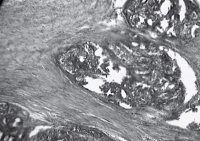

Ábra. Z. Adenocarcinoma macska mell. Színező gematoksilininom és eozin. SW. 400

Emlődaganatok macskák meglehetősen gyakori, különösen a nem-sterilizált állatok korban 5-10 év; ritka esetekben fordulhat elő fiatal állatokban legfeljebb 2 év. A túlnyomó többsége emlőtumorok macskák rosszindulatú, leggyakoribb adenokarcinóma. Ezek a tumorok áttéteket korai és gyakran visszatérnek. Prognózis függ elsősorban a tumor mérete. Ha a daganat mérete 2 cm - kedvező prognózist, 2-3 cm-es - megkérdőjelezhető, amelynek mértéke több, mint 3 cm prognózis általában kedvezőtlen.

Emlő adenokarcinóma kutyáknál (1. ábra) - rosszindulatú epiteiiális daganatot álló parenchima és stroma (4). Parenchyma saját tumorszövetben, a fő összetevője a tömegét, és meghatározzuk a növekedés és karakter. Strom beépített kötőszövet amelyben erek és idegek át. Parenchima kialakítva általában anyai szövet képződése során csíra. Stroma kialakítva a környező kötőszövet tumor csíra, amely ezt követően keresztülmegy egy bizonyos transzformációk hatása alatt a tumor parenchyma és képez vele egyetlen egész. Aljzatok adenokarcinóma falú, többnyire megfosztott izom membránok hullámos alakban, gyakran nyúlt zsúfolt vért. Nincs szigorú közötti megosztottság az artériák és vénák. Az utóbbit gyakran elé a hézagokat, amelynek fala áll az egyik endothelium. Az erek növekedését néha lemarad a turbulens proliferációs parenchyma (ábra. 2) a nem megfelelő vérellátás a tumorszövet gyakran merülnek fel elhalás (ábra. 3). Immunhisztokémiai vizsgálatok megállapították, hogy a daganat utal tumorok hormon-ösztrogén.